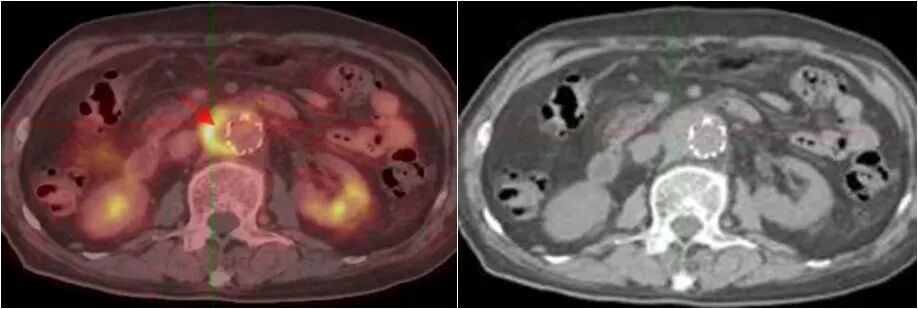

图片

右肺癌伴多发全身转移

食管癌伴淋巴结、骨、肝脏转移